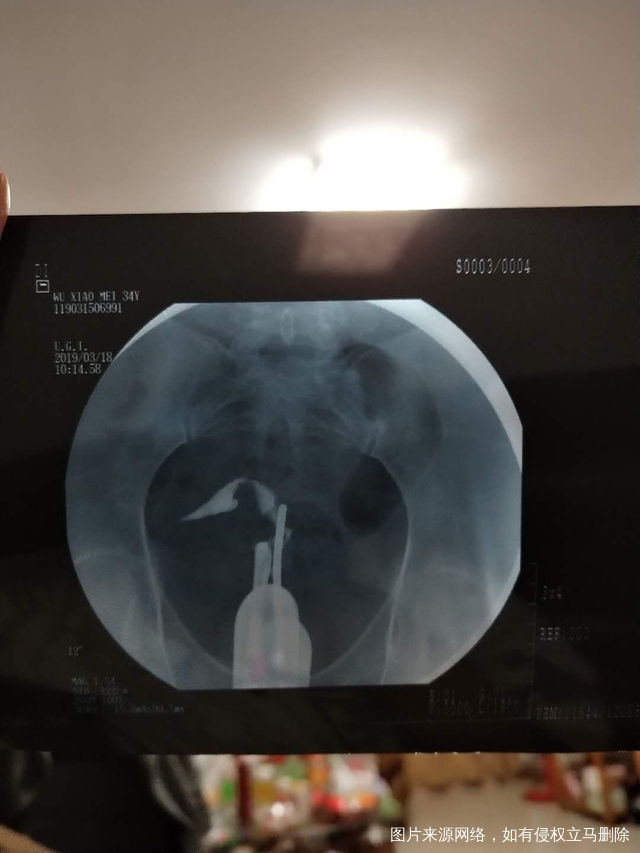

麻烦医生帮我看一下输卵管堵塞像我这样的做宫腔

做完输卵管造影第六天了小腹还是感觉沉甸甸的如

可以热敷腹部,如果有发热,腹痛加剧,白带量多,有异味,随时就医